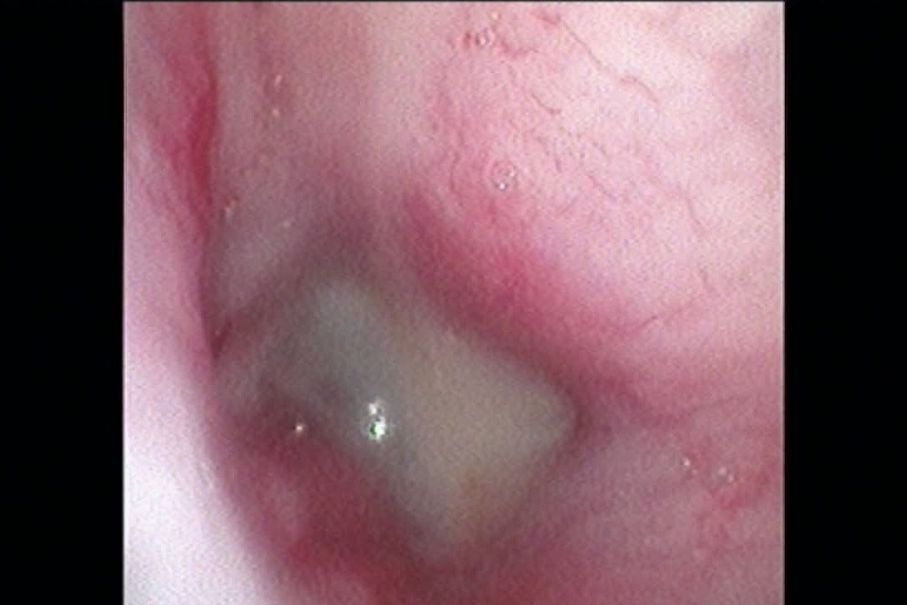

➡️深度的清潔上鼻甲及下鼻甲的分泌物, 可清楚地看見鼻道或氣道是否被甚麼組織給阻塞, 可清楚的採樣避團塊免誤傷健康鼻甲骨, 若發現異物可以立馬夾出, 肥厚或是腫瘤的阻塞可以藉由雷射進行移除, 可以針對特定的肺葉進行樣本採集

➡️除此之外, 我們還會一起評估後鼻孔.雙側耳咽管.軟顎.喉頭, 讓病原體無所遁形